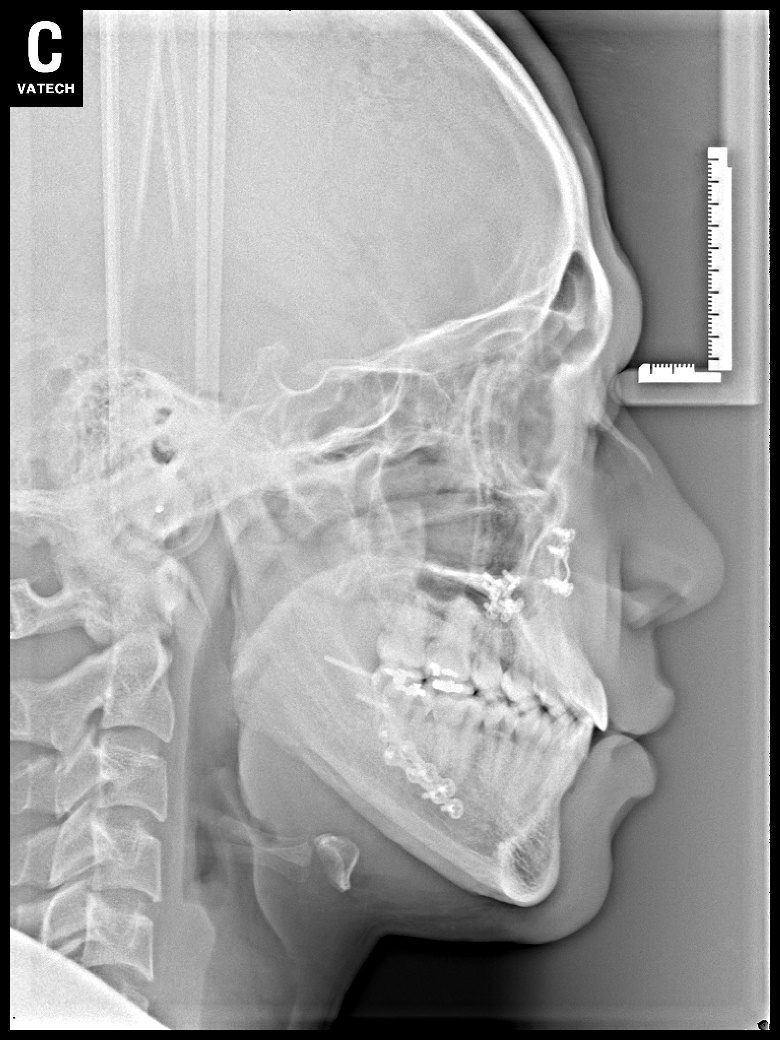

치료 전 사진입니다.